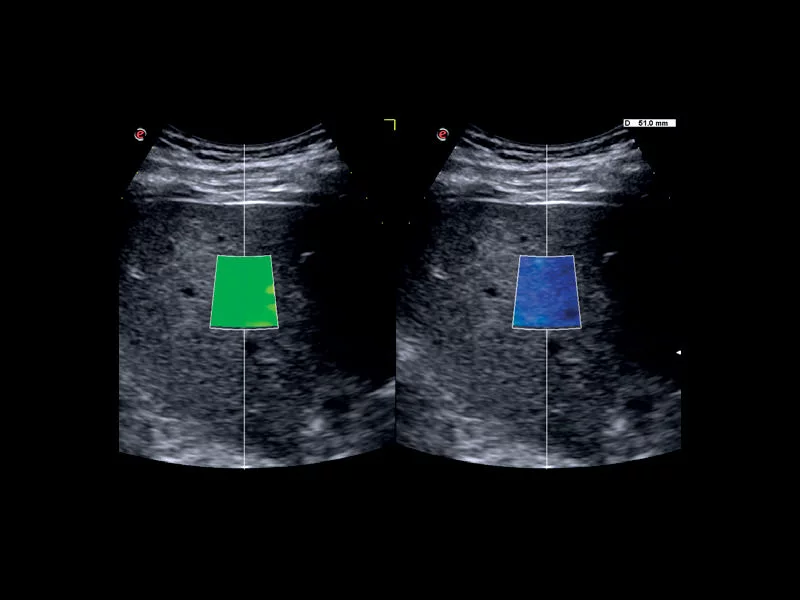

MyLab™C30 - QElaxto 2D liver

MyLab™C30 - QElaxto 2D liver